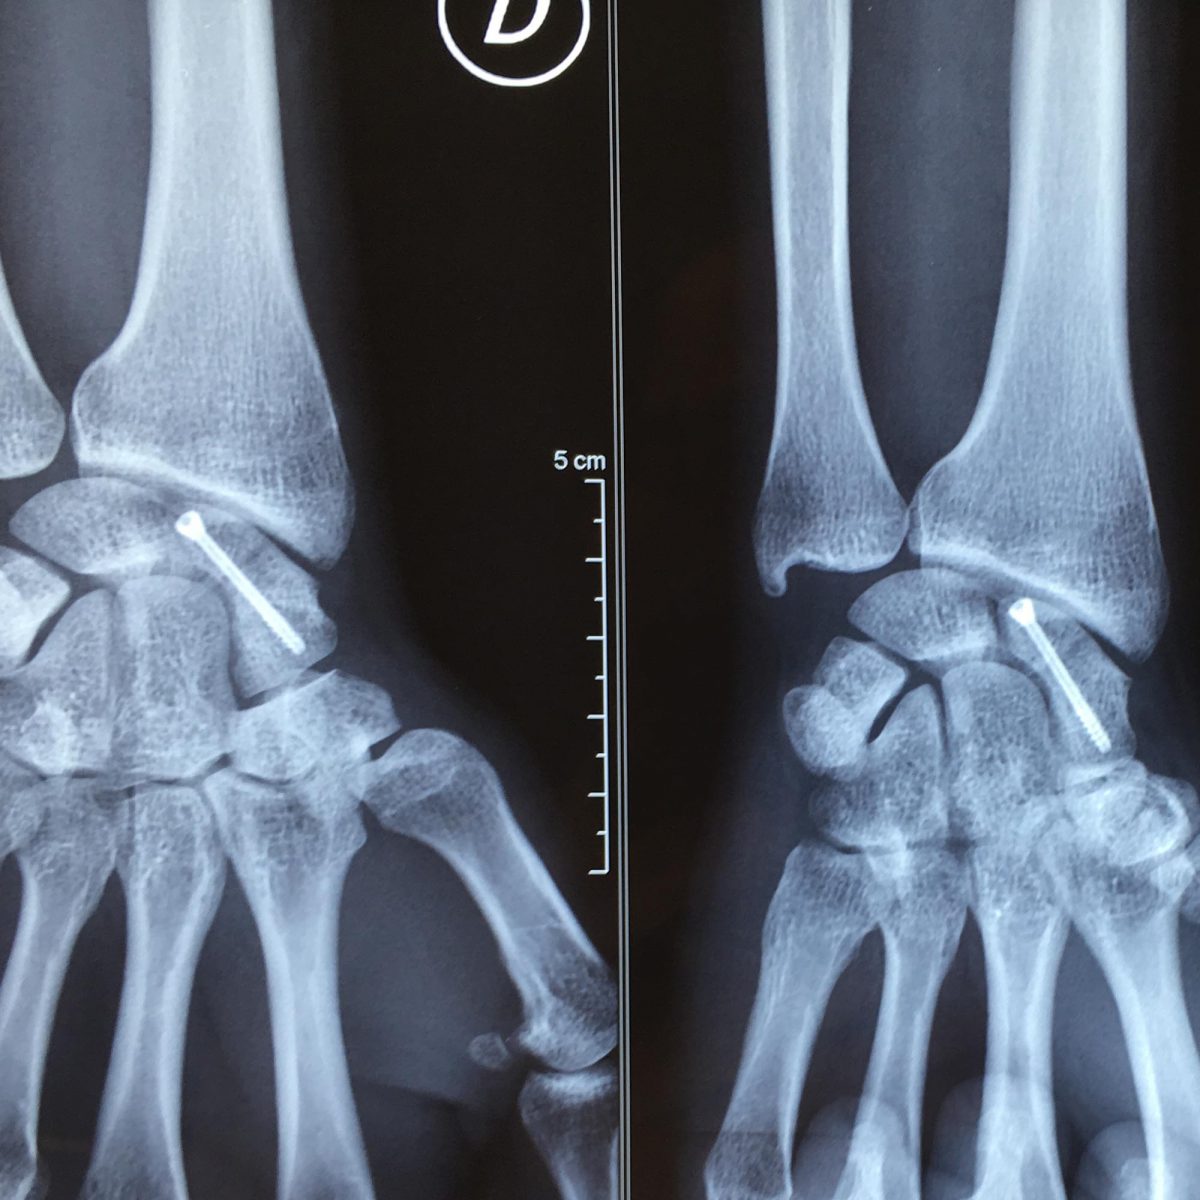

Fracture Scaphoïde Temps De Guérison. Fracture du scaphoïde Chirurgien de l'épaule et de la main Le tiers distal devrait guérir en 6-8 semaines, le tiers moyen en 8-12 semaines et le tiers proximal en 12-24 semaines La fracture du scaphoïde est une blessure fréquente, surtout chez les amateurs de sports ou lors d'accidents de la vie quotidienne

Fracture du Scaphoïde Spécialistes main et Bordeaux. Si vous avez subi une fracture du scaphoïde, vous voudrez savoir combien de temps prendra le processus de guérison, et en quoi consistera la récupération exactement.Cette blessure peut être assez délicate, car le temps de guérison varie souvent selon les cas Le scaphoïde est l'un des 8 os constitutifs du carpe, à la base du poignet, et ses fractures sont extrêmement fréquentes